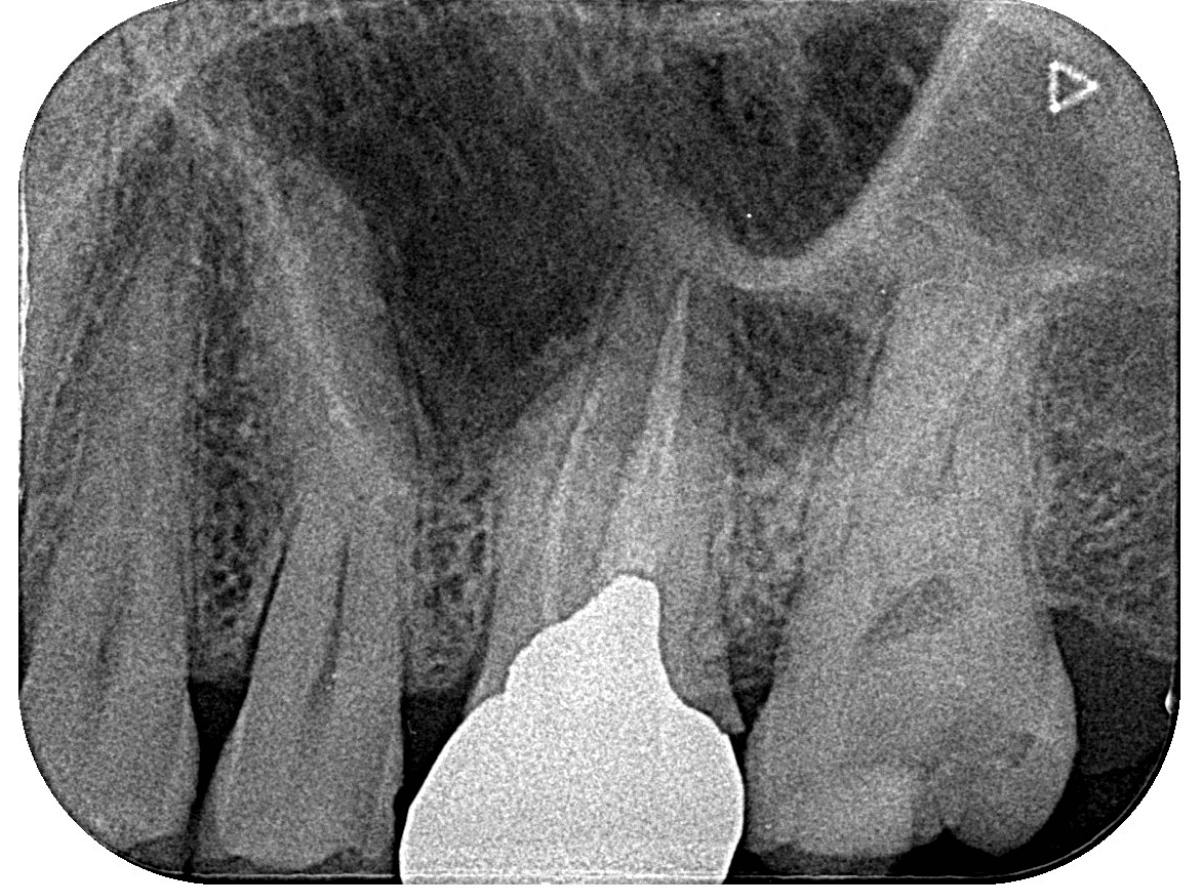

レントゲン写真です。

レジンの下が虫歯になっているのがわかります。

レントゲン写真で確認します。

青い線が歯の神経、赤い線が虫歯です。

おやしらずがあった際にはわかりづらかったですが、歯の後ろ側のおやしらずが重なっていたところが虫歯になっているのがわかります。